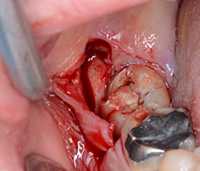

親知らずが骨の中に埋まっている場合には、局所麻酔を行い、歯肉を切開し、歯の周囲の骨を削除します。傾斜している親知らずの場合には、歯を分割して抜歯します。抜歯後は縫合し、翌日に消毒、1週間後に抜糸します。通常は外来通院で行いますが、歯が深く骨に埋まっている場合には、入院全身麻酔下で行うこともあります。